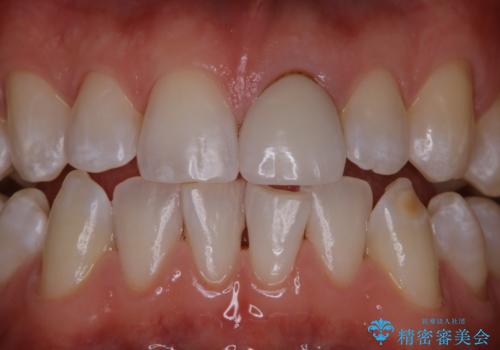

[前歯 セラミック治療] すぐに前歯が取れる きちんと治療して欲しい

![[前歯 セラミック治療] すぐに前歯が取れる きちんと治療して欲しいの症例 治療前](https://seimitsushinbi.jp/wp/wp-content/uploads/2021/01/9e6ce61e0bdd79ba9b3792484754c3e3-500x350.jpg?v=1609914925)

![[前歯 セラミック治療] すぐに前歯が取れる きちんと治療して欲しいの症例 治療後](https://seimitsushinbi.jp/wp/wp-content/uploads/2021/01/1c3b62c3a0de497eade34ec62d821d52-500x350.jpg?v=1609914963)